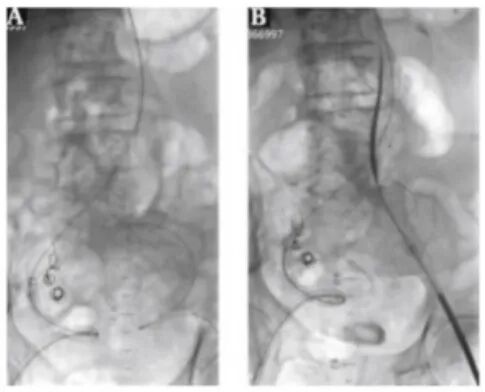

PE+Corpassing泊淮™ 大鞘

血管鞘组是什么器械百科丨Corpassing泊淮™ 导管鞘组_https://www.jmylbn.com_新闻资讯_第11张

EVAR+Corpassing泊淮™ 大鞘

血管鞘组是什么器械百科丨Corpassing泊淮™ 导管鞘组_https://www.jmylbn.com_新闻资讯_第13张